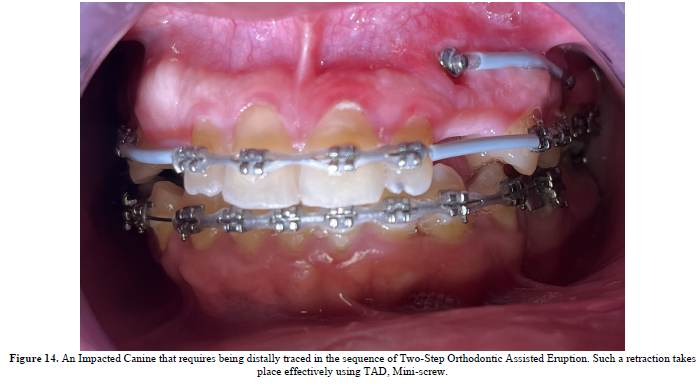

TADs are of a paramount importance within treatment of scissors-bites (Figure 9,10), scheming the treatment plan is supposed to include the TADs pulling (Figure 11,12 & 13).

- Impacted Teeth Treatment using TADs:

Thanks to TADs as they move the needle in the Orthodontic Assisted Treatments if Impacted Teeth.

Especially when the impacted unit requites two-step orthodontic eruption, the Temporary Anchorage Device deprecates the adjacent teeth movements; decrease the negative flaws of the impacted unit(s) on the juxtaposed dental units.

Bearing the whole burden of the traction forces placates the aftermaths of the existence of the impacted dental unit(s), dwindles such negative consequences into zero (Figure 14).